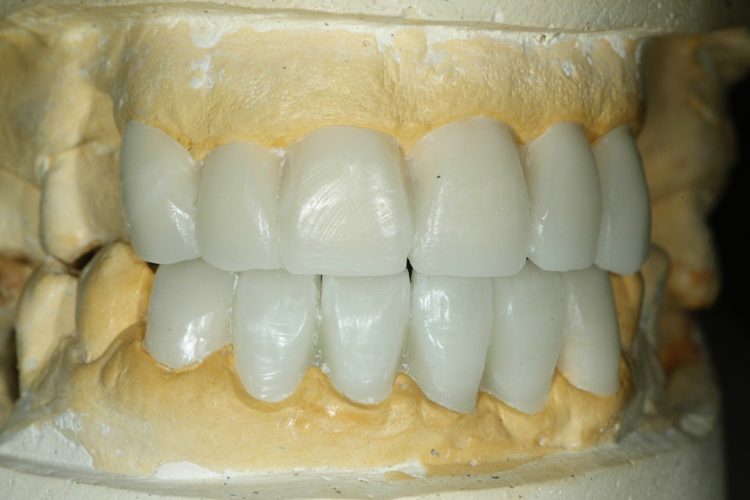

Caso Clínico:  Ponte metalo-cerâmica com 10 elementos sobre dentes e implantes em paciente com perda de 6 dentes no  maxilar superior Descrição: Paciente com 50 anos com perda de 6 dentes no maxilar superior descontente com a prótese removível que possui e com uma com aparência estética desfavorável que pretende uma reabilitação fixa funcional e uma